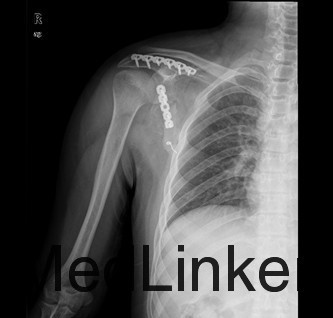

诊断:右肩胛骨粉碎性骨折 治疗:拟行右肩胛骨骨折切开复位内固定术

肩胛体部骨折主要为直接暴力引起,如重物或火器伤直接损伤肩胛骨体部,多为粉碎性骨折,有时亦有横行或斜行骨折,因肩胛骨前后均有肌肉保护,多无明显骨折移位,但须注意有无肋骨骨折或胸腔脏器伤。